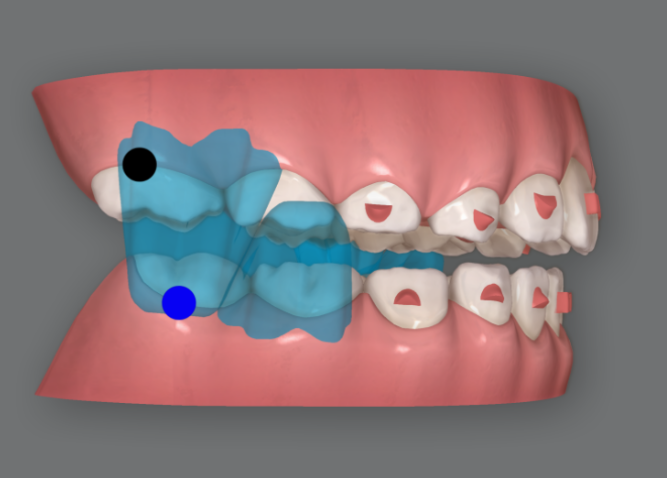

26단계부터 57단계 까지는 아래턱의 위치를 유도하는 MA 단계이고 장치모습을 보면 파란색으로 표기된 <윙>이 위아래 각각 두쌍씩 튀어나와 있는 것이 보입니다.

23.09

실제로 입안에서는 이렇게 구현이 됩니다.

아래턱을 내밀어서 물지 않으면 윙끼리 간섭때문에 입이 다물리지 않습니다.

앞에서 보면 이런 모습입니다.